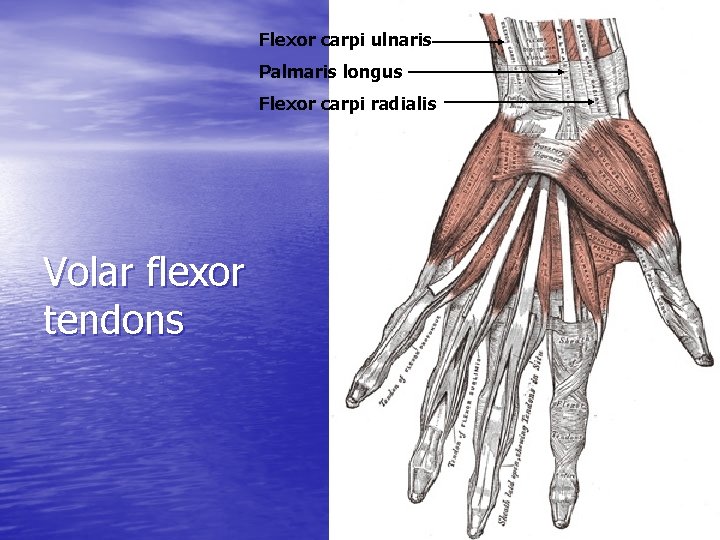

Flexor carpi ulnaris Palmaris longus Flexor carpi radialis Volar flexor tendons